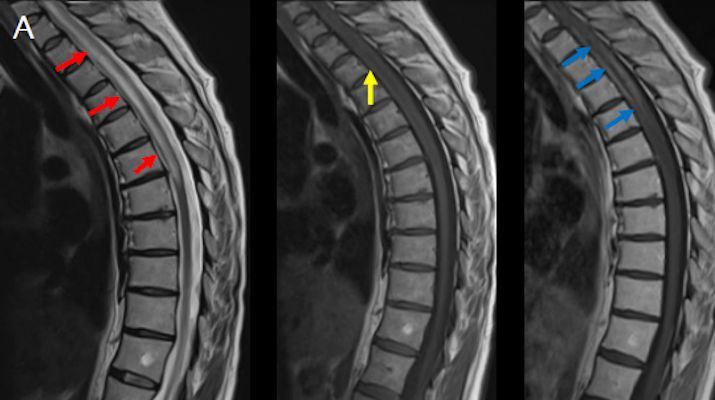

- (A) Torakal MRG’de sagital görüntülerde üst-orta torakal düzeyde T2A hiperintens (oklar), T1A izo-hipointens (ok) uzun segment ekspansil sinyal değişikliği izlenmekte olup sagital postkontrast T1A’da kontrast tutulumu mevcuttur (oklar). Bulgular longitudinal ekstensif transvers miyelit (LETM) ile uyumludur.

Görüntüleme Bulguları

- Transvers miyelit sıklıkla santral gri cevheri etkileyen ve üç veya daha fazla vertebral gövde uzunluğunu etkilemektedir (LETM).

- Omurilik atrofisi ve ekspansiyon/ödem MS’e göre daha fazla görülür.

- Kontrast madde enjeksiyonu sonrasında neredeyse tüm akut NMO lezyonları, yamalı, düzensiz veya periferik olarak kontrastlanma gösterir.